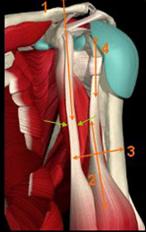

INSERTIA TENDONULUI COMUN AL MUSCHIULUI PSOAS ILIAC

Tendonul terminal al muschiului iliac se termina pe fata anterioara si laterala

a muschiului psoas. Tendonul comun al m. psoas iliac se insera pe trohanterul mic